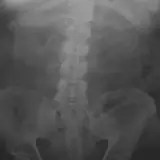

Over 2,100 interactive radiology cases, curated by radiologists for your level of training. Scroll, window, and view cases full screen โ€” just like on PACS. Click linked findings in each writeup to jump straight to them on the image. Cases include sample reports, a focused discussion section, original illustrations, and videos.

Casi completamente interattivi con gli strumenti che ti aspetti su un PACS: scroll, windowing, zoom, pan, misurazioni, ROI e modalitร  a schermo intero.

Annotazioni dettagliate evidenziano i reperti chiave direttamente sui casi. Clicca sui reperti collegati nella descrizione del caso per saltare alla loro esatta posizione sullo scan.